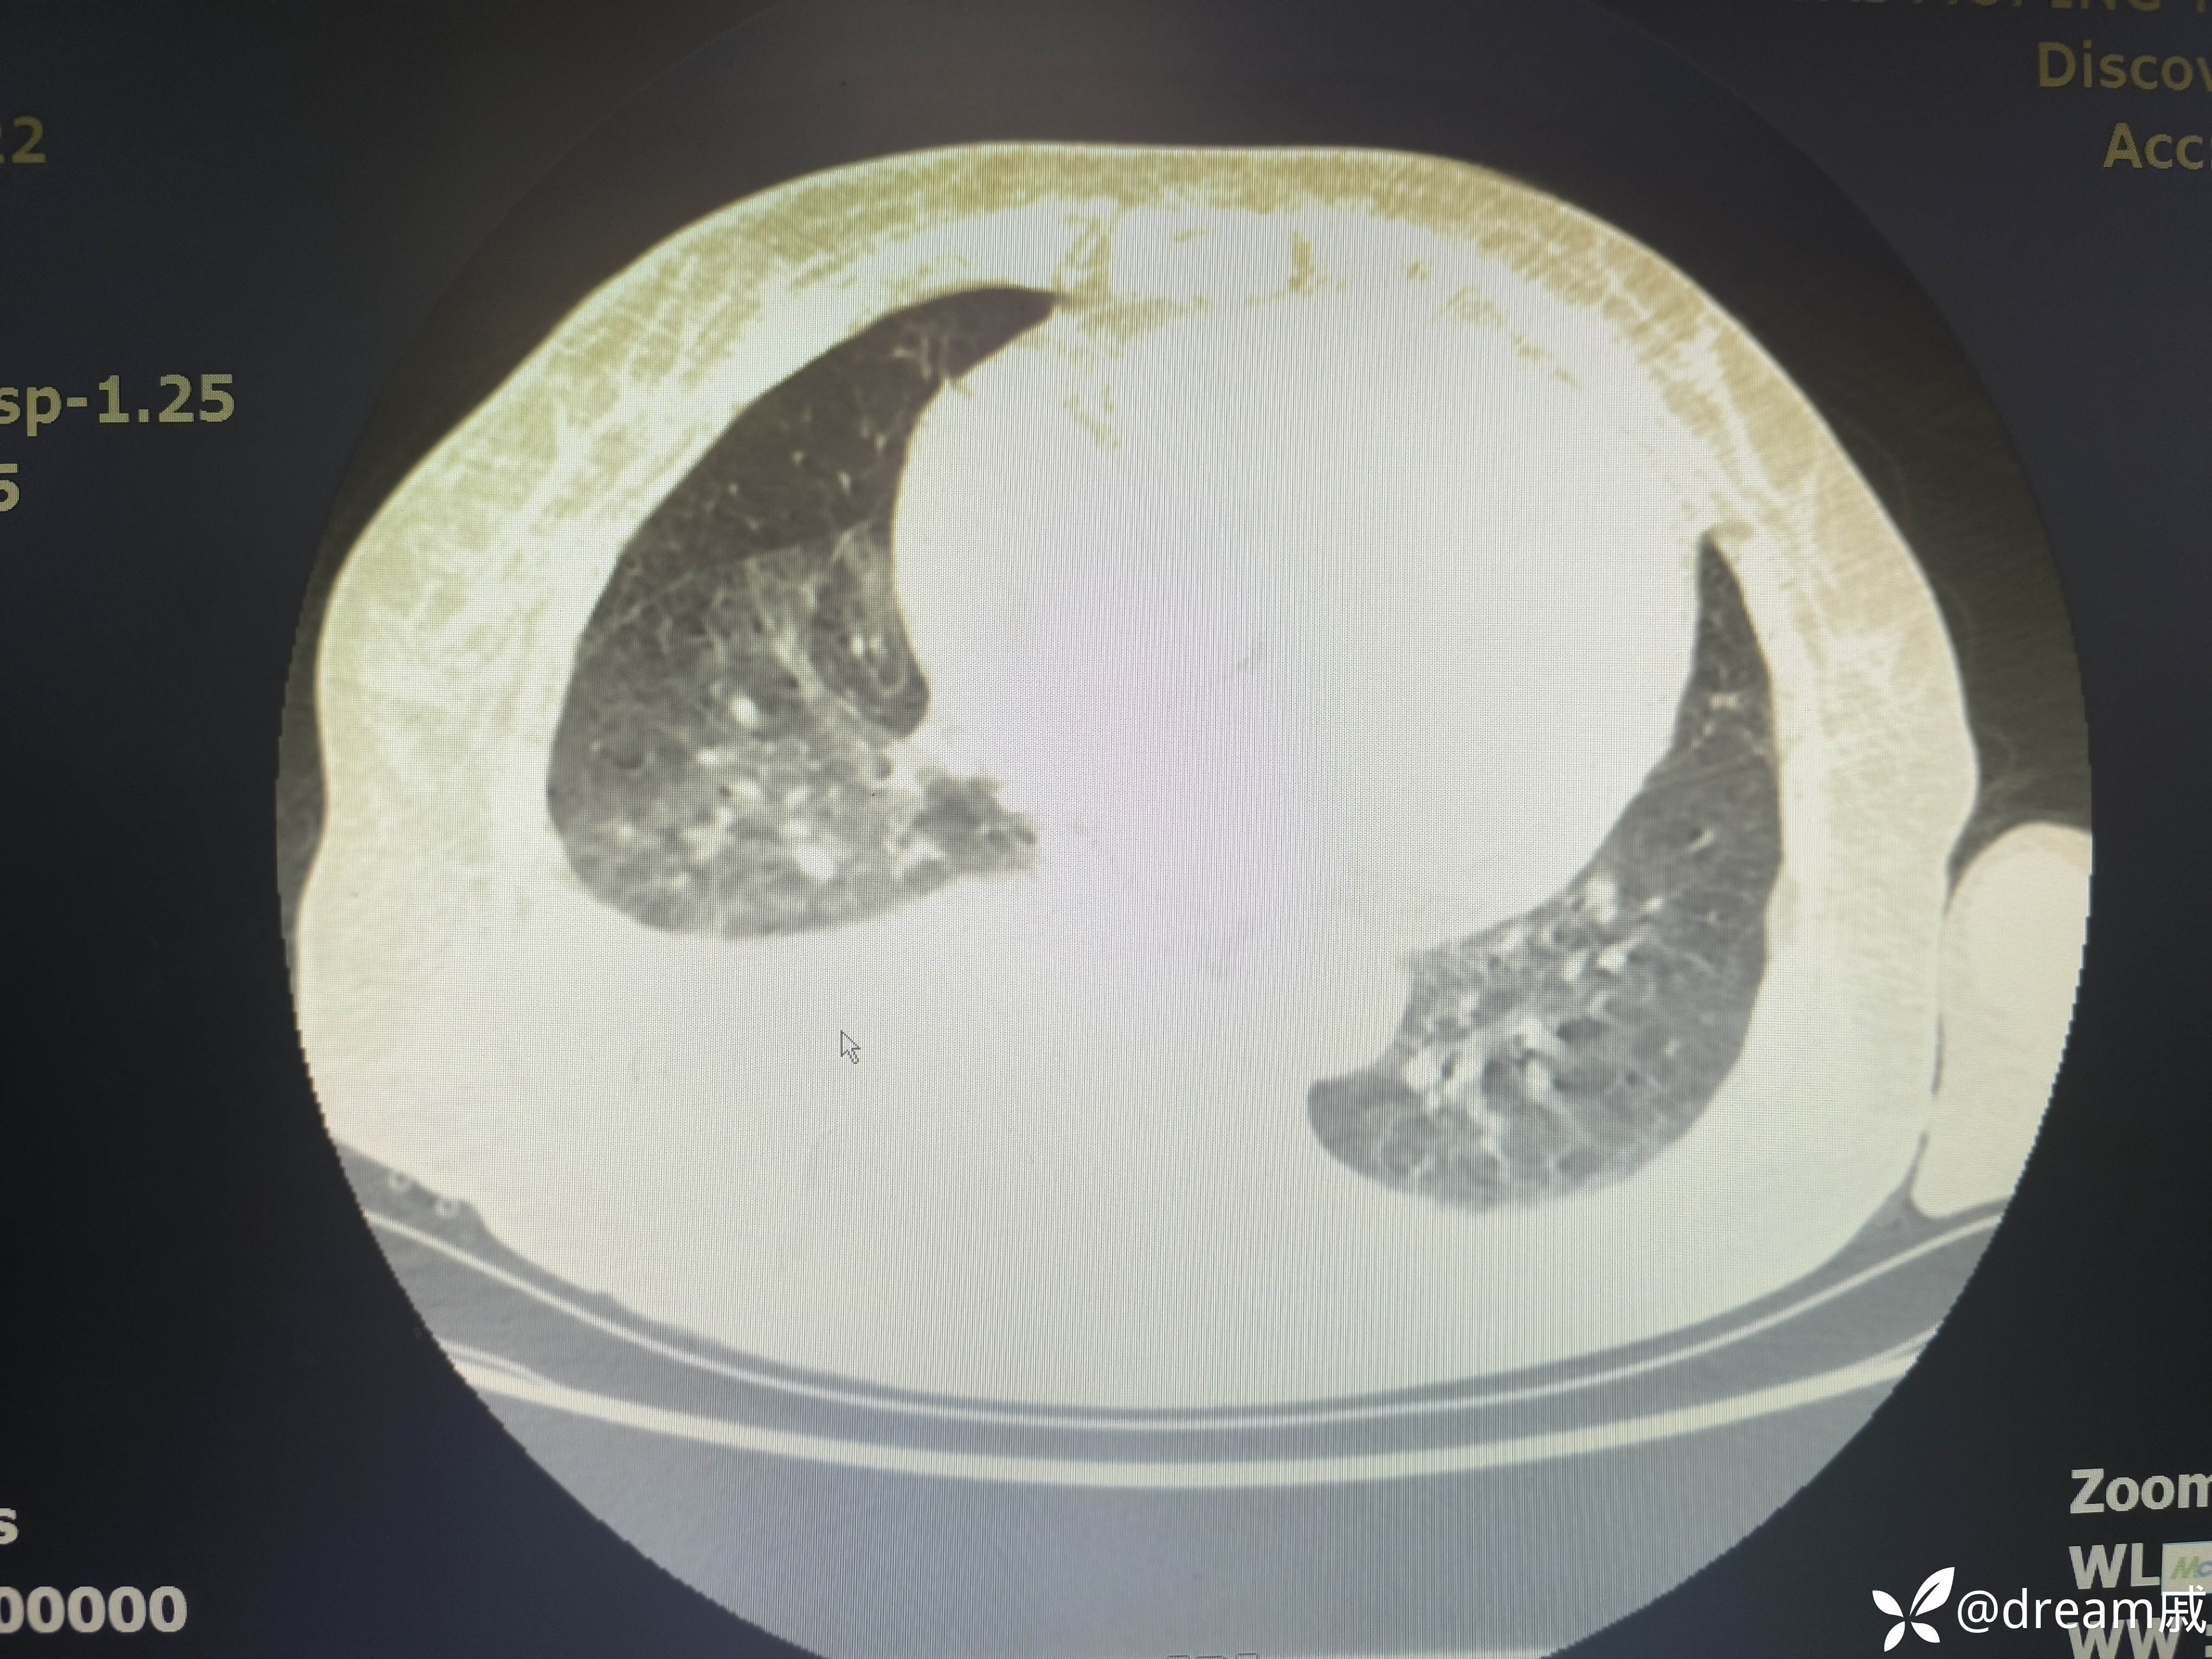

胸部CT示右肺中下叶斑片影,双肺局部间质性改变。

5月27日复查CT如下